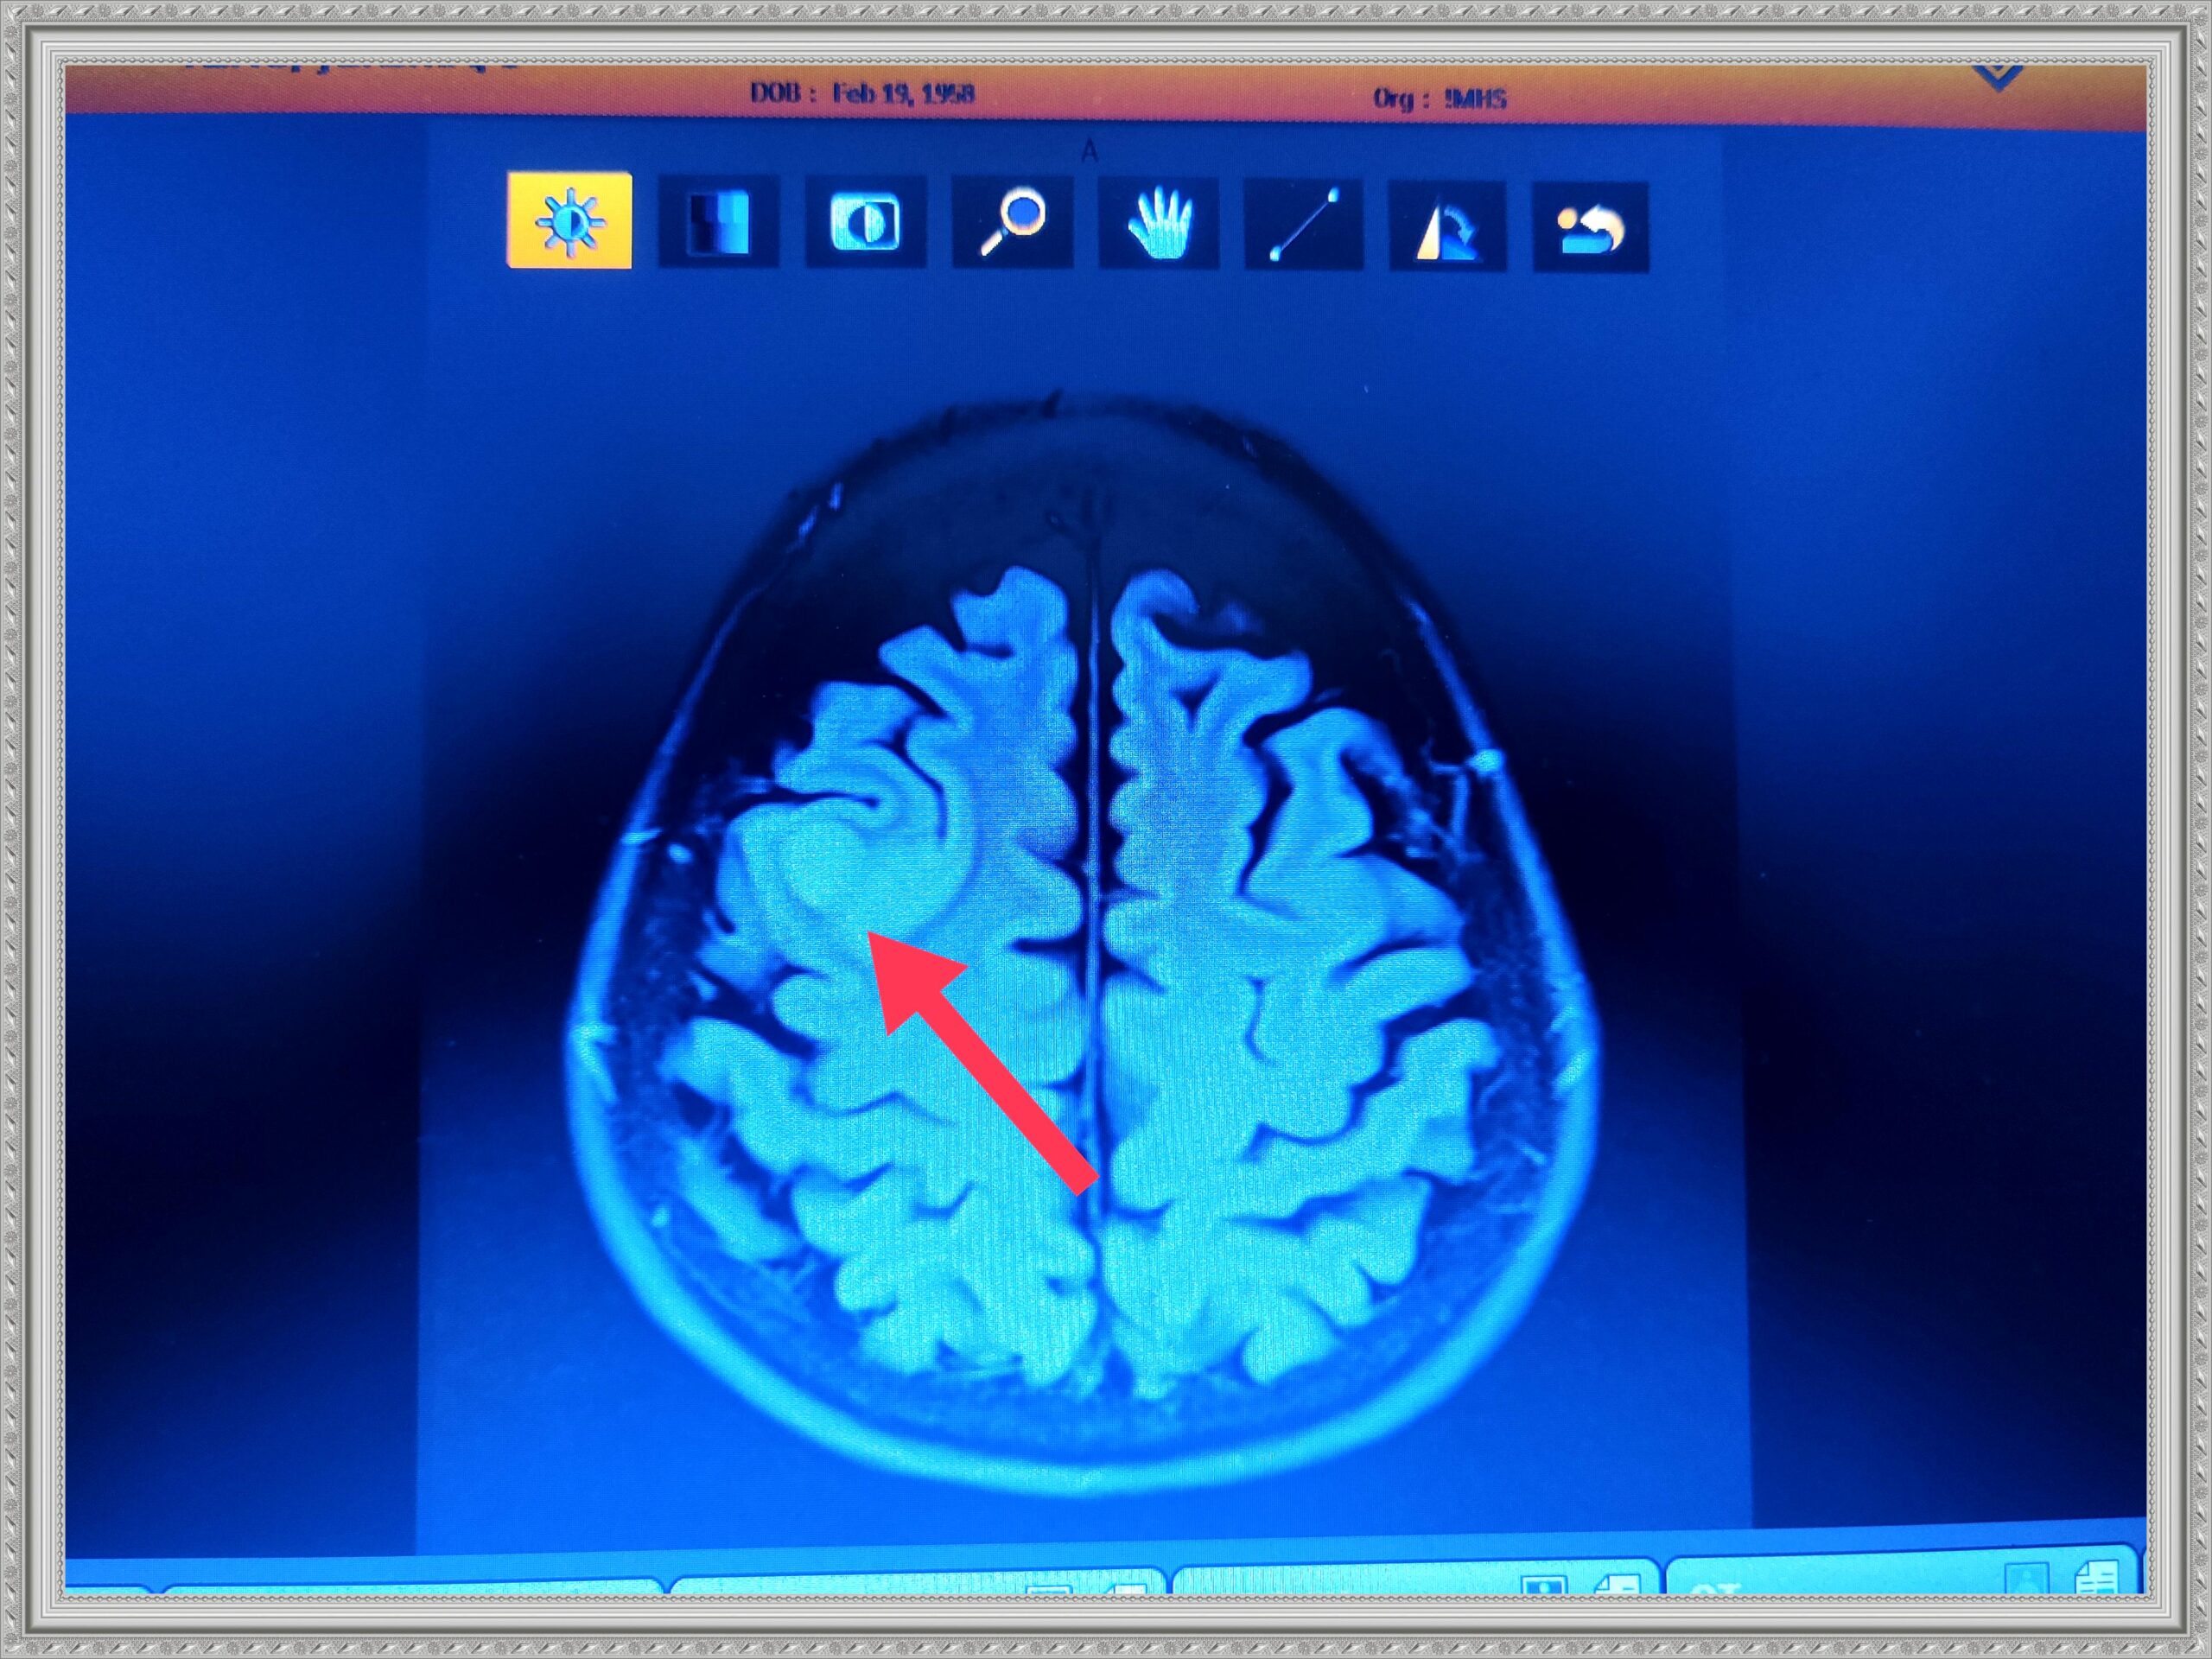

The next gallery shows me at Memorial Central Hospital in Colorado Springs after having surgery to remove my tumor and staying for a few weeks after for Physical, Speech and Occupational Therapy. The staff there was so AWESOME! I hold every one of them dear to my heart.

Me Recovering from Brain Cancer Surgery